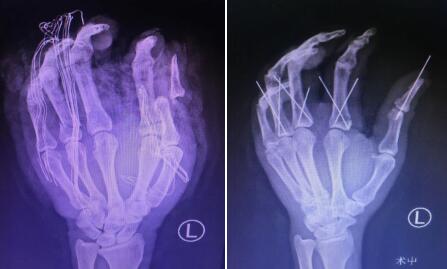

下午2点左右,当他做完检查,距离他受伤已经过去了5个小时。检查结果显示其左手多发指骨骨折、第三掌骨骨折、多发血管损伤、神经损伤、肌腱、肌肉损伤、皮肤挫伤……患者看完检查结果,再次恳求唐医生:“医生,您帮帮我!”

唐洪伟医生手术团队为患者进行了“左手清创,骨折及脱位复位内固定、血管神经肌腱肌肉韧带撕脱皮肤修复+血管移植术”。尽管接通血运的难度较大,手术团队克服困难,一一接通血管、神经和肌腱。经过3个多小时,手术顺利完成。